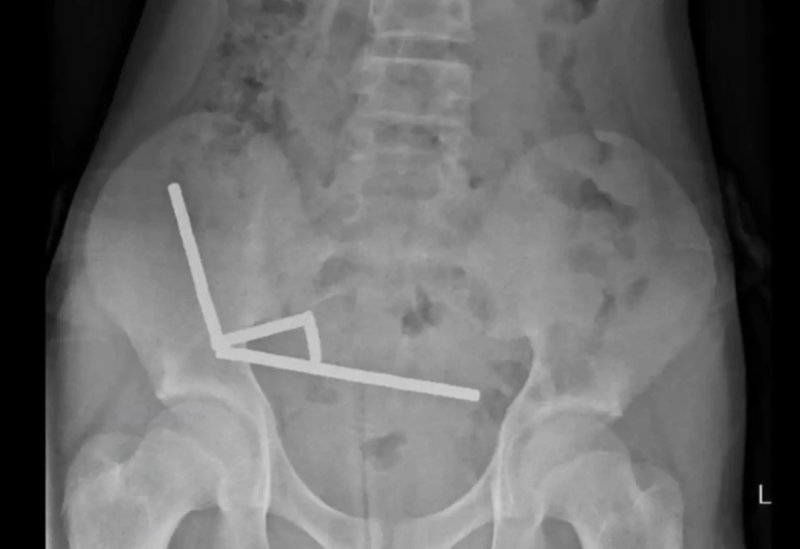

[뉴시스] 엑스레이 촬영 결과 자석이 장 내에서 뭉쳐 인근 조직의 혈류를 차단한 것으로 나타났다. (사진=뉴욕포스트) 2025.10.24.

의료진은 엑스레이 검사에서 그의 장 속에 약 200개의 작은 네오디뮴 자석이 사슬 형태로 뭉쳐 있는 것을 발견했다.

이 자석들은 서로 강하게 끌어당기며 장 벽을 압박해 혈류를 차단했고, 그 결과 장 점막 일부가 괴사했다.